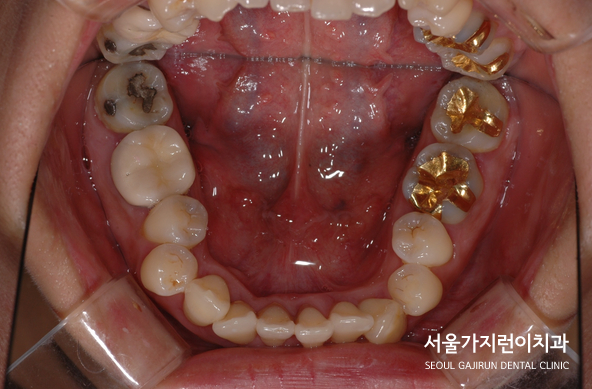

환자분의 경우 전반적인 치조골의 소실이 심한 상태셨는데요. 발치 공간을 폐쇄하는 과정에서 빈 공간으로 치아들이 잘 쓰러지기 때문에 교정치료에 들어가기 전 잇몸 염증을 선 치료한 후 교정 치료 중에 발생할 수 있는 상하악 구치의 수직적 정출이 일어나지 않도록 치료를 할 필요가 있었습니다. 그래서 본원에서는 설측교정을 통해 제2대 구치의 설측교두의 수직적 정출 가능성을 줄여보았는데요. 결과적으로 하악의 시계 방향 회전 가능성이 줄어들어 상악에 미니스크류를 식립해 교정치료를 진행했습니다. 미니스크류를 사용하게 되면 상악 제 2대구치 설측교두의 정출을 막는 정도가 아니라 함임시키기 때문에 하악골이 반시계방향으로 회전하도록 만들 수 있는데요. 이렇게 하면 무턱 증상도 개선해볼 수 있습니다.

즉, 치조골소 실이 상당히 진행된 경우라고 해도 치료 전 염증 조절만 잘하면 교정치료를 받아볼 수 있는데요. 다른 교정치과에서 교정이 힘들다는 답변을 받았어도 설측교정장치를 이용해 치아교정을 마무리한 환자분의 전후 사진입니다. 만약 이 글을 읽고 있는 여러분도 교정이 어렵다는 답변을 들었다면 본원을 방문해 언제든 상담 받아보시기 바랍니다. 연구와 치료를 거듭해온 서울가지런이치과 교정과 의원에서 주걱턱/돌출입/심한덧니 치료, 치아교정을 통해 개선해보시기 바랍니다.